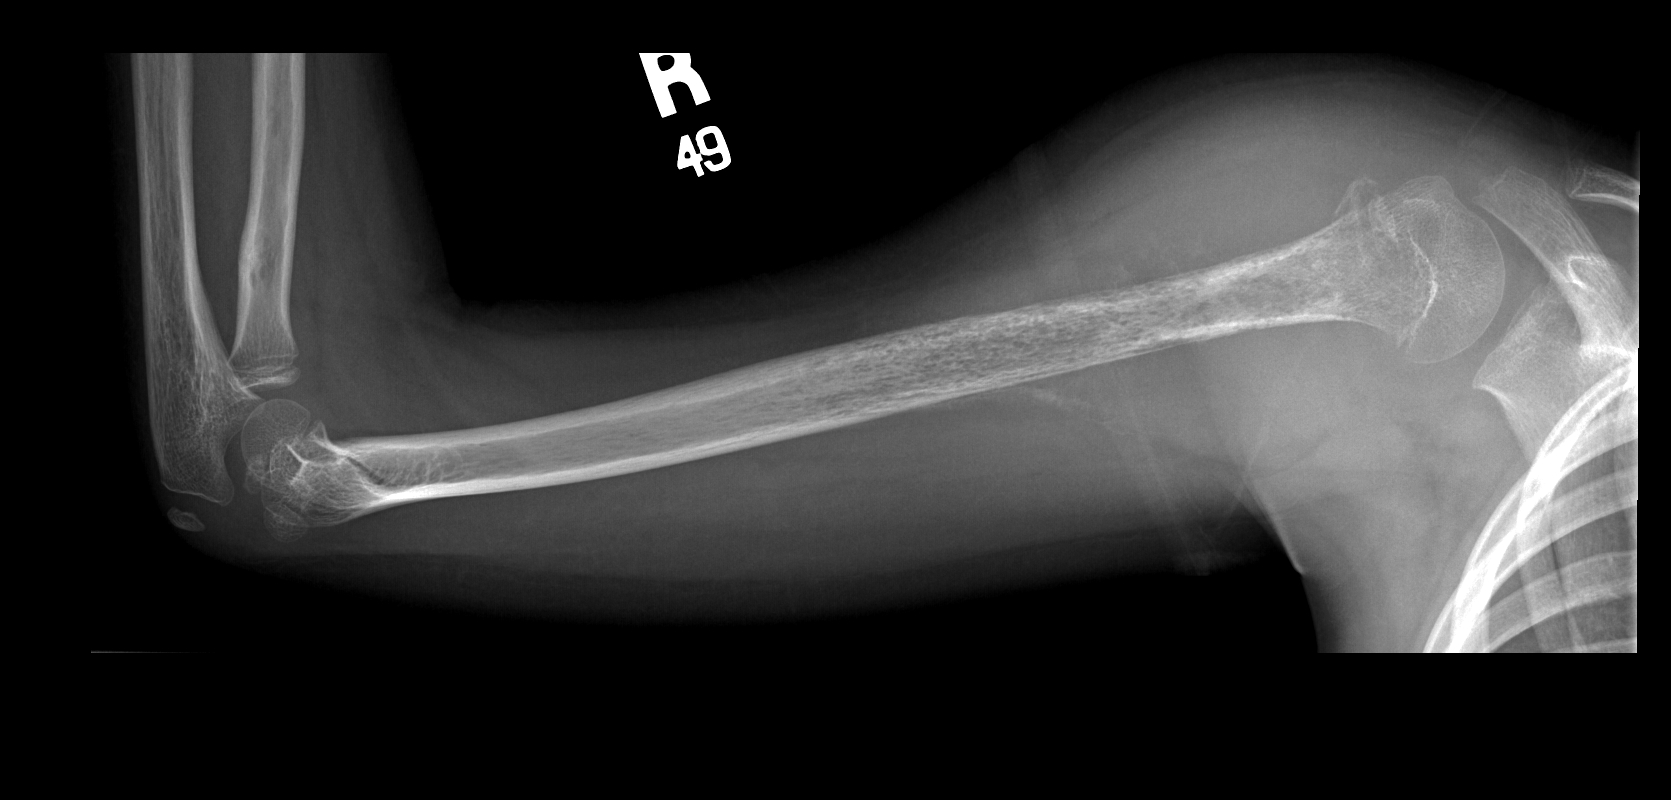

Рентгеновские снимки саркомы плечевого сустава